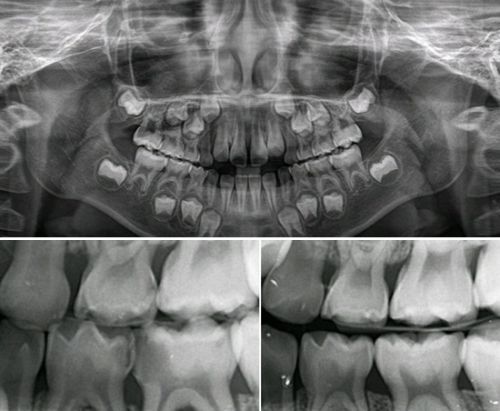

파노라마 방사선 사짐 및 치아사이의 충치를 검사하는 교익사진

파노라마 방사선 사진 및 치아 사이의 충치를 검사하는 교익사진 /전승준

그리고 이어서 빠질 수 없는 검사가 바로 방사선 검사입니다. 구강 내에서 촬영하는 작은 엑스레이 사진부터, 턱 전체를 찍는 파노라마 사진, 치과용 컴퓨터단층방사선사진(CT)까지 종류가 다양합니다. 육안으로는 볼 수 없는 치아 속 구조나 잇몸뼈 상태, 혹은 염증이나 낭종 같은 병적인 상태를 파악하는 데 꼭 필요한 검사입니다.